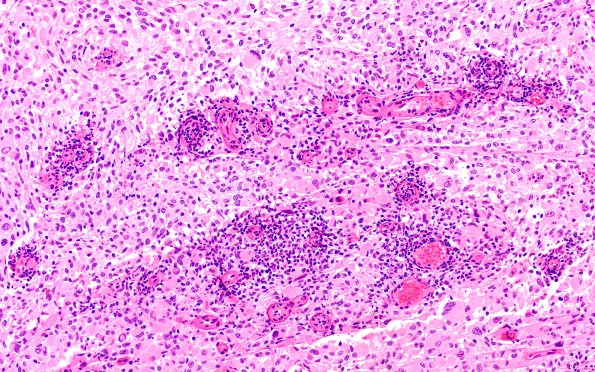

Washington University Experience | NEOPLASMS (GLIAL) | Pleomorphic Xanthoastrocytoma (PXA) | 22B3B PXA (Case 22) H&E 20X 3

The perivascular elements consist of numerous lymphocytes and a striking infiltrate of myeloid cells and PMNs along with scattered perivascular lymphocytic chronic inflammation and microcalcifications. (H&E)